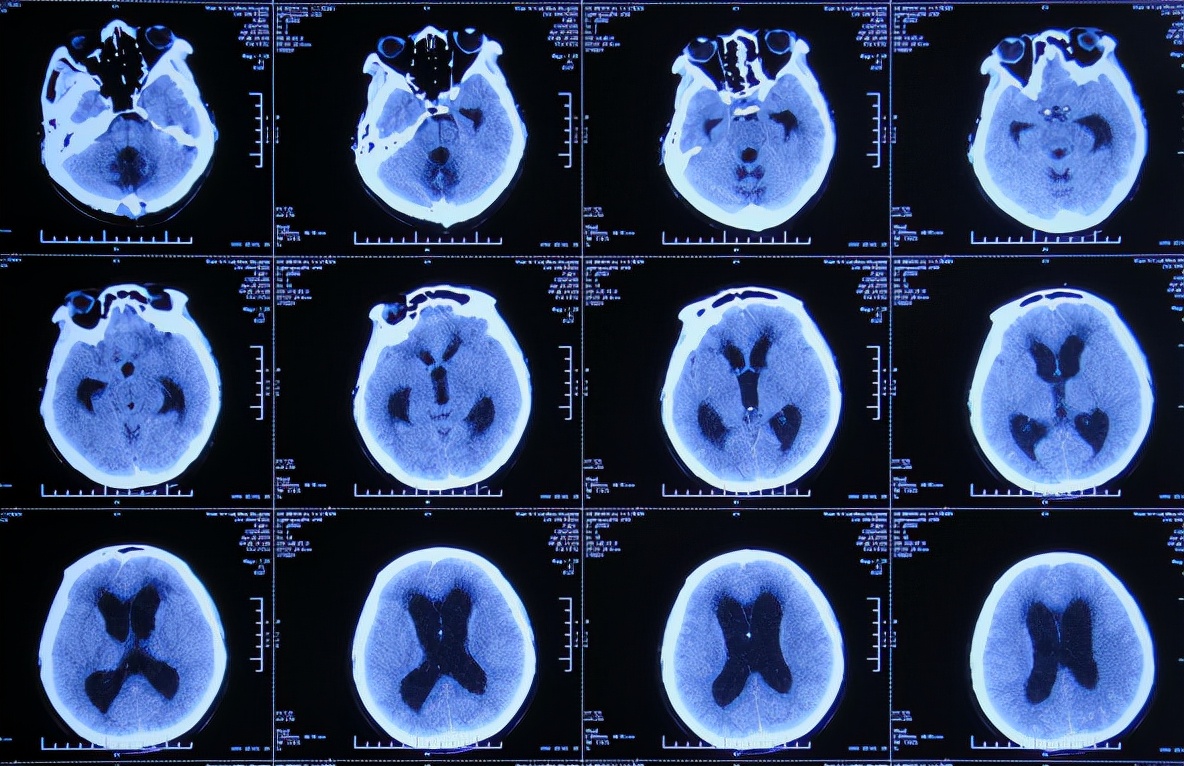

患者2019年2月18日下午,睡觉时突然出现剧烈头痛,持续无缓解,于是就诊于当地的山西省文水县某医院,查头颅CT示小脑出血破入脑室( 图-1 );考虑出血量不多,住院保守治疗。

图-1: 2019年2月18日头颅CT

但1小时后出现意识障碍加重,复查头颅CT( 图-2 )示小脑出血增多,急诊进行了左侧脑室穿刺外引流术+后颅窝血肿清除;术后住入重症监护室。

图-2: 2019年2月18日头颅CT02

脑出血脑室外引流术后次日即2019年2月19日,复查头颅CT示出血未见明显减少( 图-3 )。

图-3: 2019年2月19日头颅CT

但脑出血脑室外引流术3天即2019年2月21日,出现尿崩症状,查头颅CT示脑室仍有出血( 图-4 );给予口服弥凝2天后症状好转,查血电解质示低钠、低钾,但给予积极纠正但效果仍不理想。

图-4: 2019年2月21日头颅CT

脑出血脑室外引流术7天即2019年2月25日,查头颅CT示出血明显好转( 图-5 )。

图-5: 2019年2月25日头颅CT

脑出血脑室外引流术12天即2019年3月2日,查头颅CT示出血完全消失,但脑室稍有扩大( 图-6 )。

图-6: 2019年3月2日头颅CT